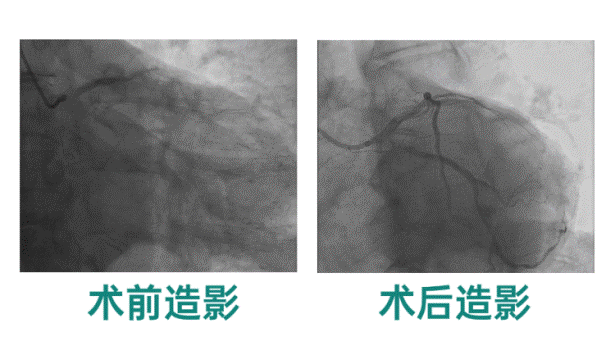

【佳木斯大學(xué)宏大醫(yī)院】 “火眼金睛” 精準(zhǔn)治療!